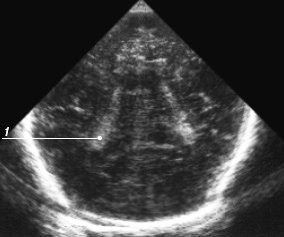

Аксиальное сканирование. Аксиальный срез выполняется при размещении датчика горизонтально над ухом. При этом визуализируются ножки мозга как гипоэхогенная структура, имеющая вид бабочки (рис. 18). Между ножками часто (в отличие от корональных и сагиттальных срезов) видна эхогенная структура, состоящая из двух точек - сильвиев водопровод, кпереди от ножек - щелевидный III желудочек. На аксиальном срезе стенки III желудочка видны отчетливо, в отличие от коронального, что позволяет более точно измерить его размер при незначительном расширении. При наклоне датчика в сторону свода черепа видны боковые желудочки, что позволяет оценить их размер при закрытом большом родничке. В норме парен хима мозга тесно прилежит к костям черепа у зрелых детей, поэтому разделение эхосигналов от них на аксиальном срезе позволяет предположить наличие патологической жидкости в субарахноидальном или субдуральном пространствах.

Рис. 18. Эхограмма мозга, аксиальный срез на уровне основания мозга.

1 - мозжечок;

2 - сильвиев водопровод;

3 - ножки мозга;

4 - сильвиева щель;

5 - III желудочек.